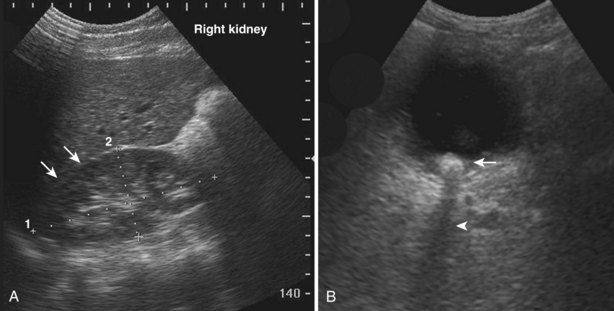

Renal size changes over the lifetime of an individual. Nomograms for pediatric renal size should be consulted. These are based on age, height, and weight of the patient. The average adult kidney measures 10 to 12 cm in length and 4 to 5 cm in width. Measurements of renal volume may be appropriate in cases of severe renal impairment. Renal measurements should be obtained in the midsagittal plane and midtransverse plane. Measurements taken in other than the midsagittal plane and midtransverse may be spuriously low. The thickness of the parenchyma is the average distance between the renal capsule and the central band of echoes. The precise location for making this measurement is somewhat subjective. The midlateral renal parenchyma in the sagittal view is a common choice for obtaining this measurement (Fig. 4–33). Although there is no universal standard, the renal cortical thickness should be greater than 7 mm (Roger et al, 1994), and the renal parenchymal thickness should be greater than 15 mm in adults (Emamian et al, 1993b).

Figure 4–33 The distinction between renal cortical thickness and renal parenchymal thickness is that the renal parenchyma is measured from the central band of echoes to the renal capsule. The renal cortex is measured from the outer margin of the medullary pyramid to the renal capsule.